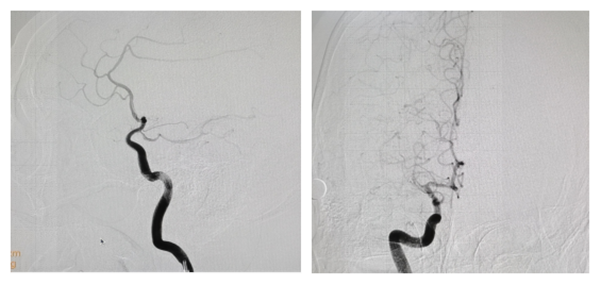

术前造影显示右侧大脑中动脉M1段闭塞